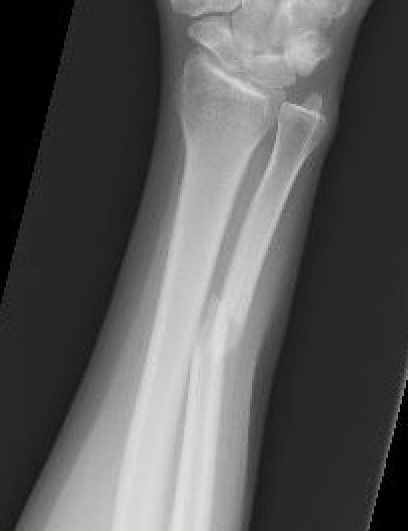

Night stick injury - direct blow or trauma to ulna

Distal 1/3

Midshaft / middle 1/3

Proximal - beware Monteggia / radial head dislocation

Minimally displaced fractures

- < 50% displaced

- < 10 degrees angulation